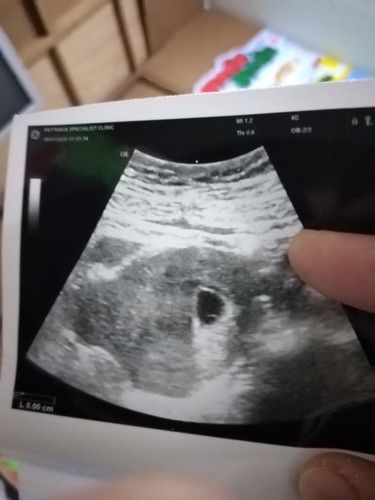

เมื่อวานไปหาหมอ เนื่องจสกปวดท้องด้านขวามากหมอซาวและถ่ายภาพมา แม่ๆคนอื่นปวดท้องบ้างไหมจ้ะ เราเป็นคนอ้วนก่อนท้อง90โลเลยค่ะ